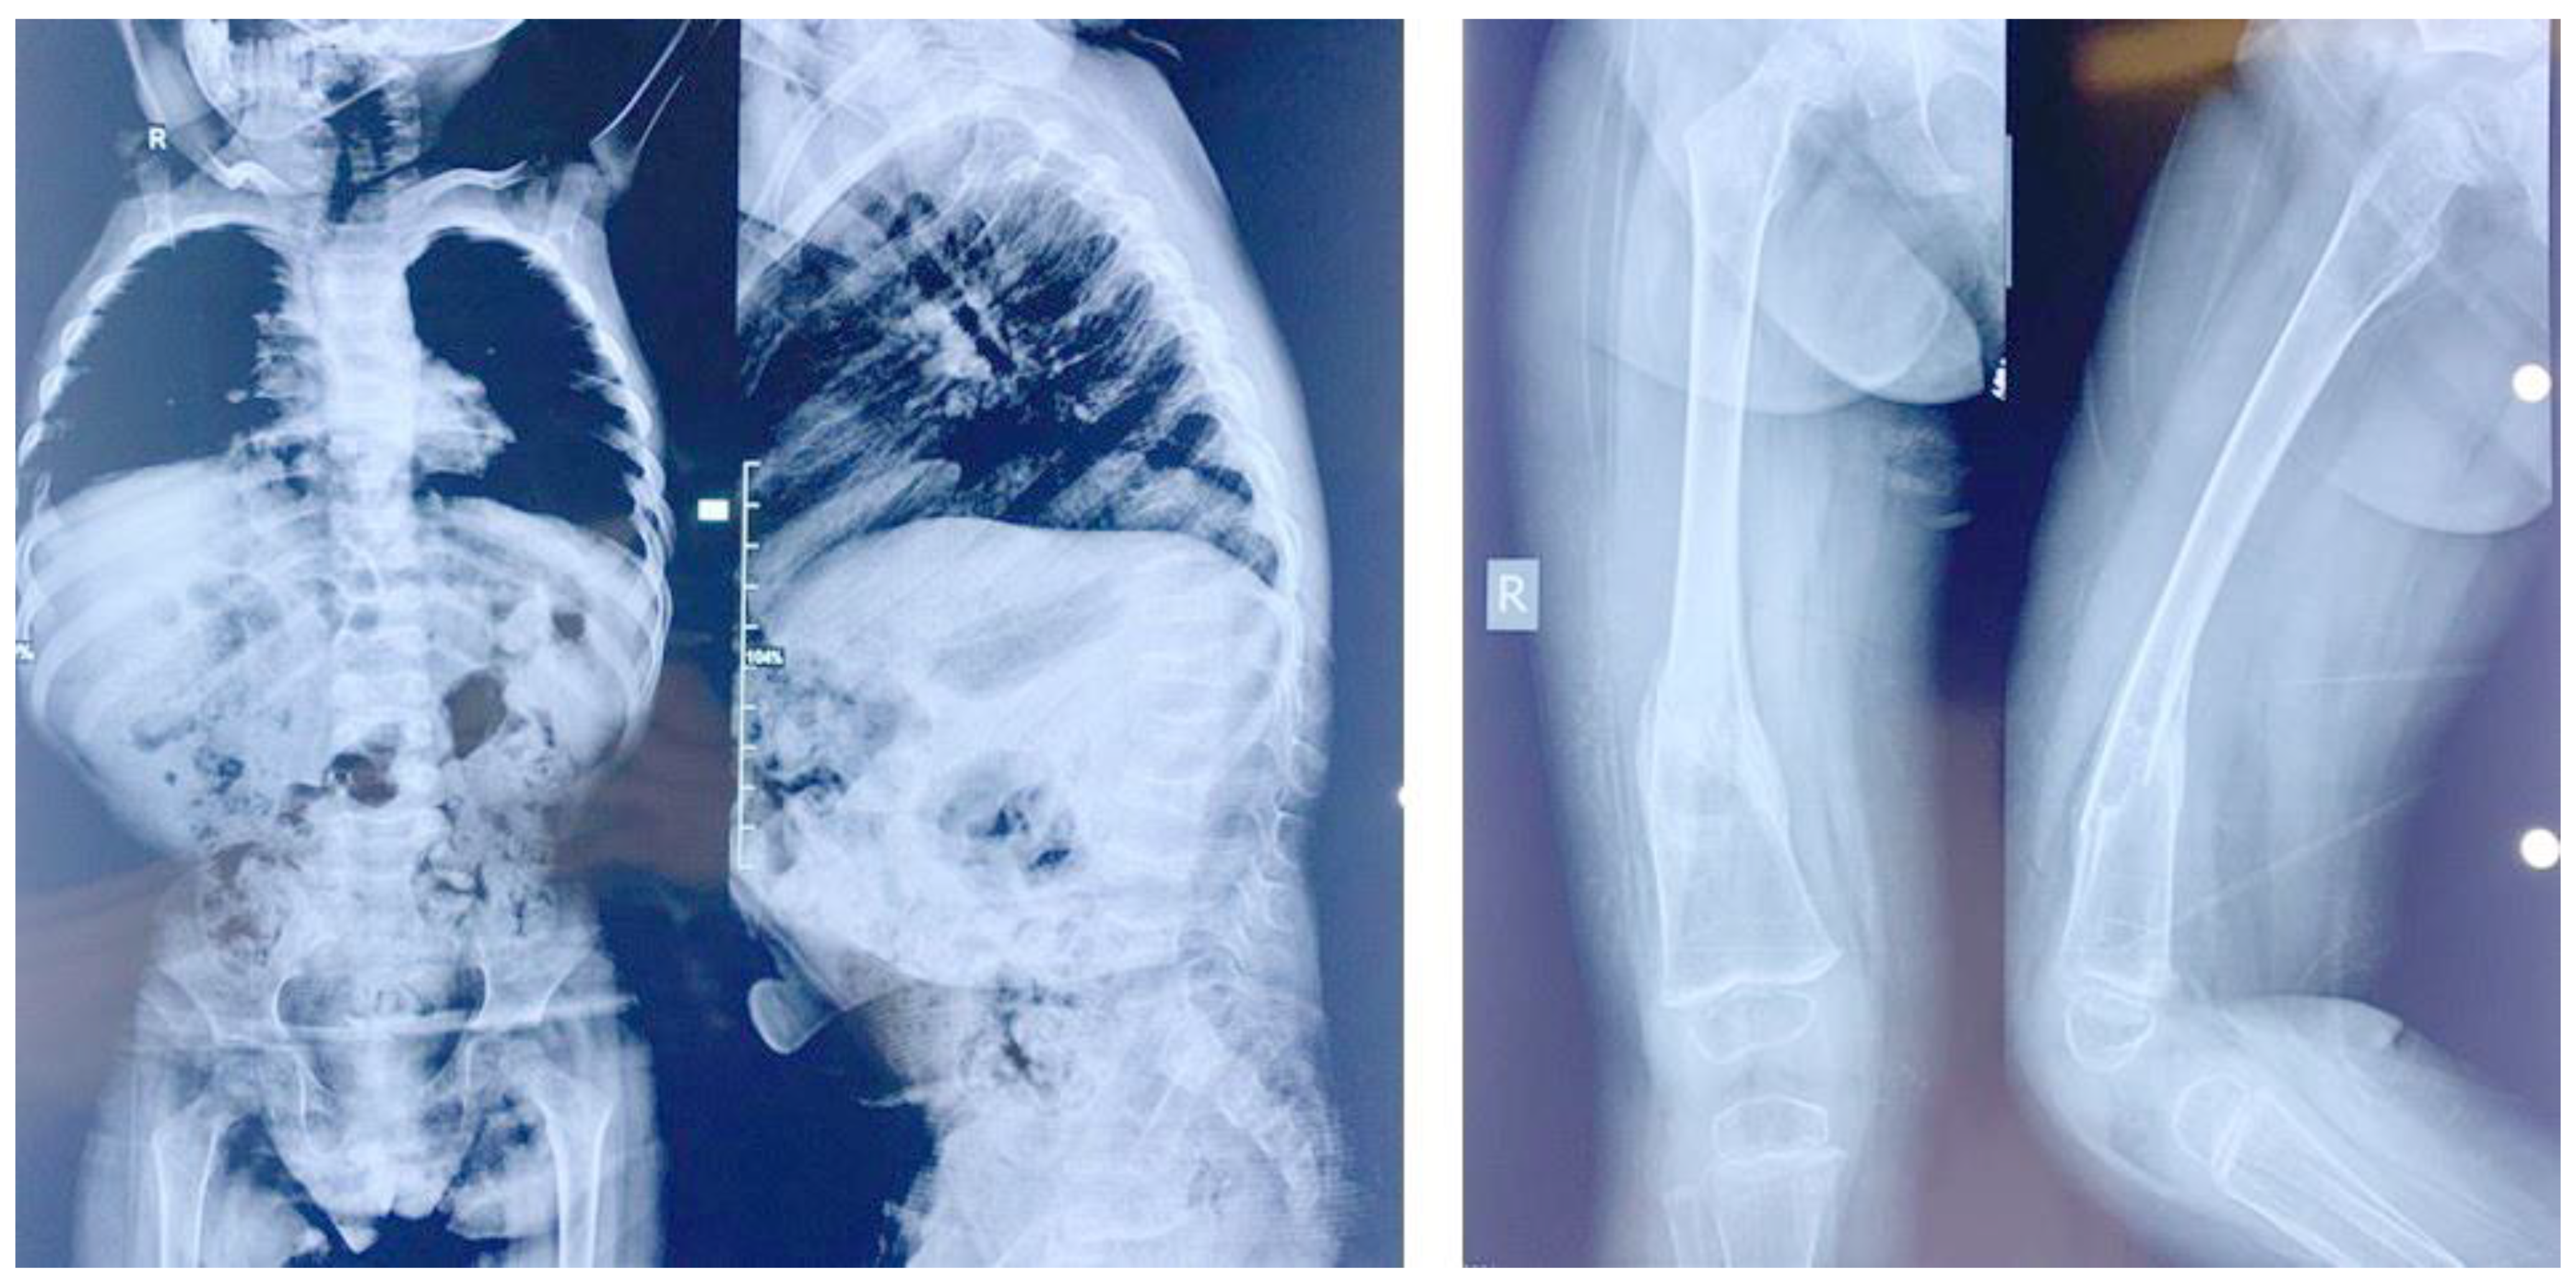

3.1. Clinical Presentations